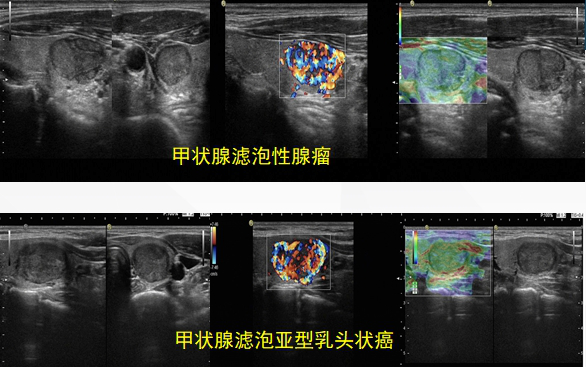

3.甲状腺滤泡状癌的超声表现有特征性吗?超声诊断靠谱吗?